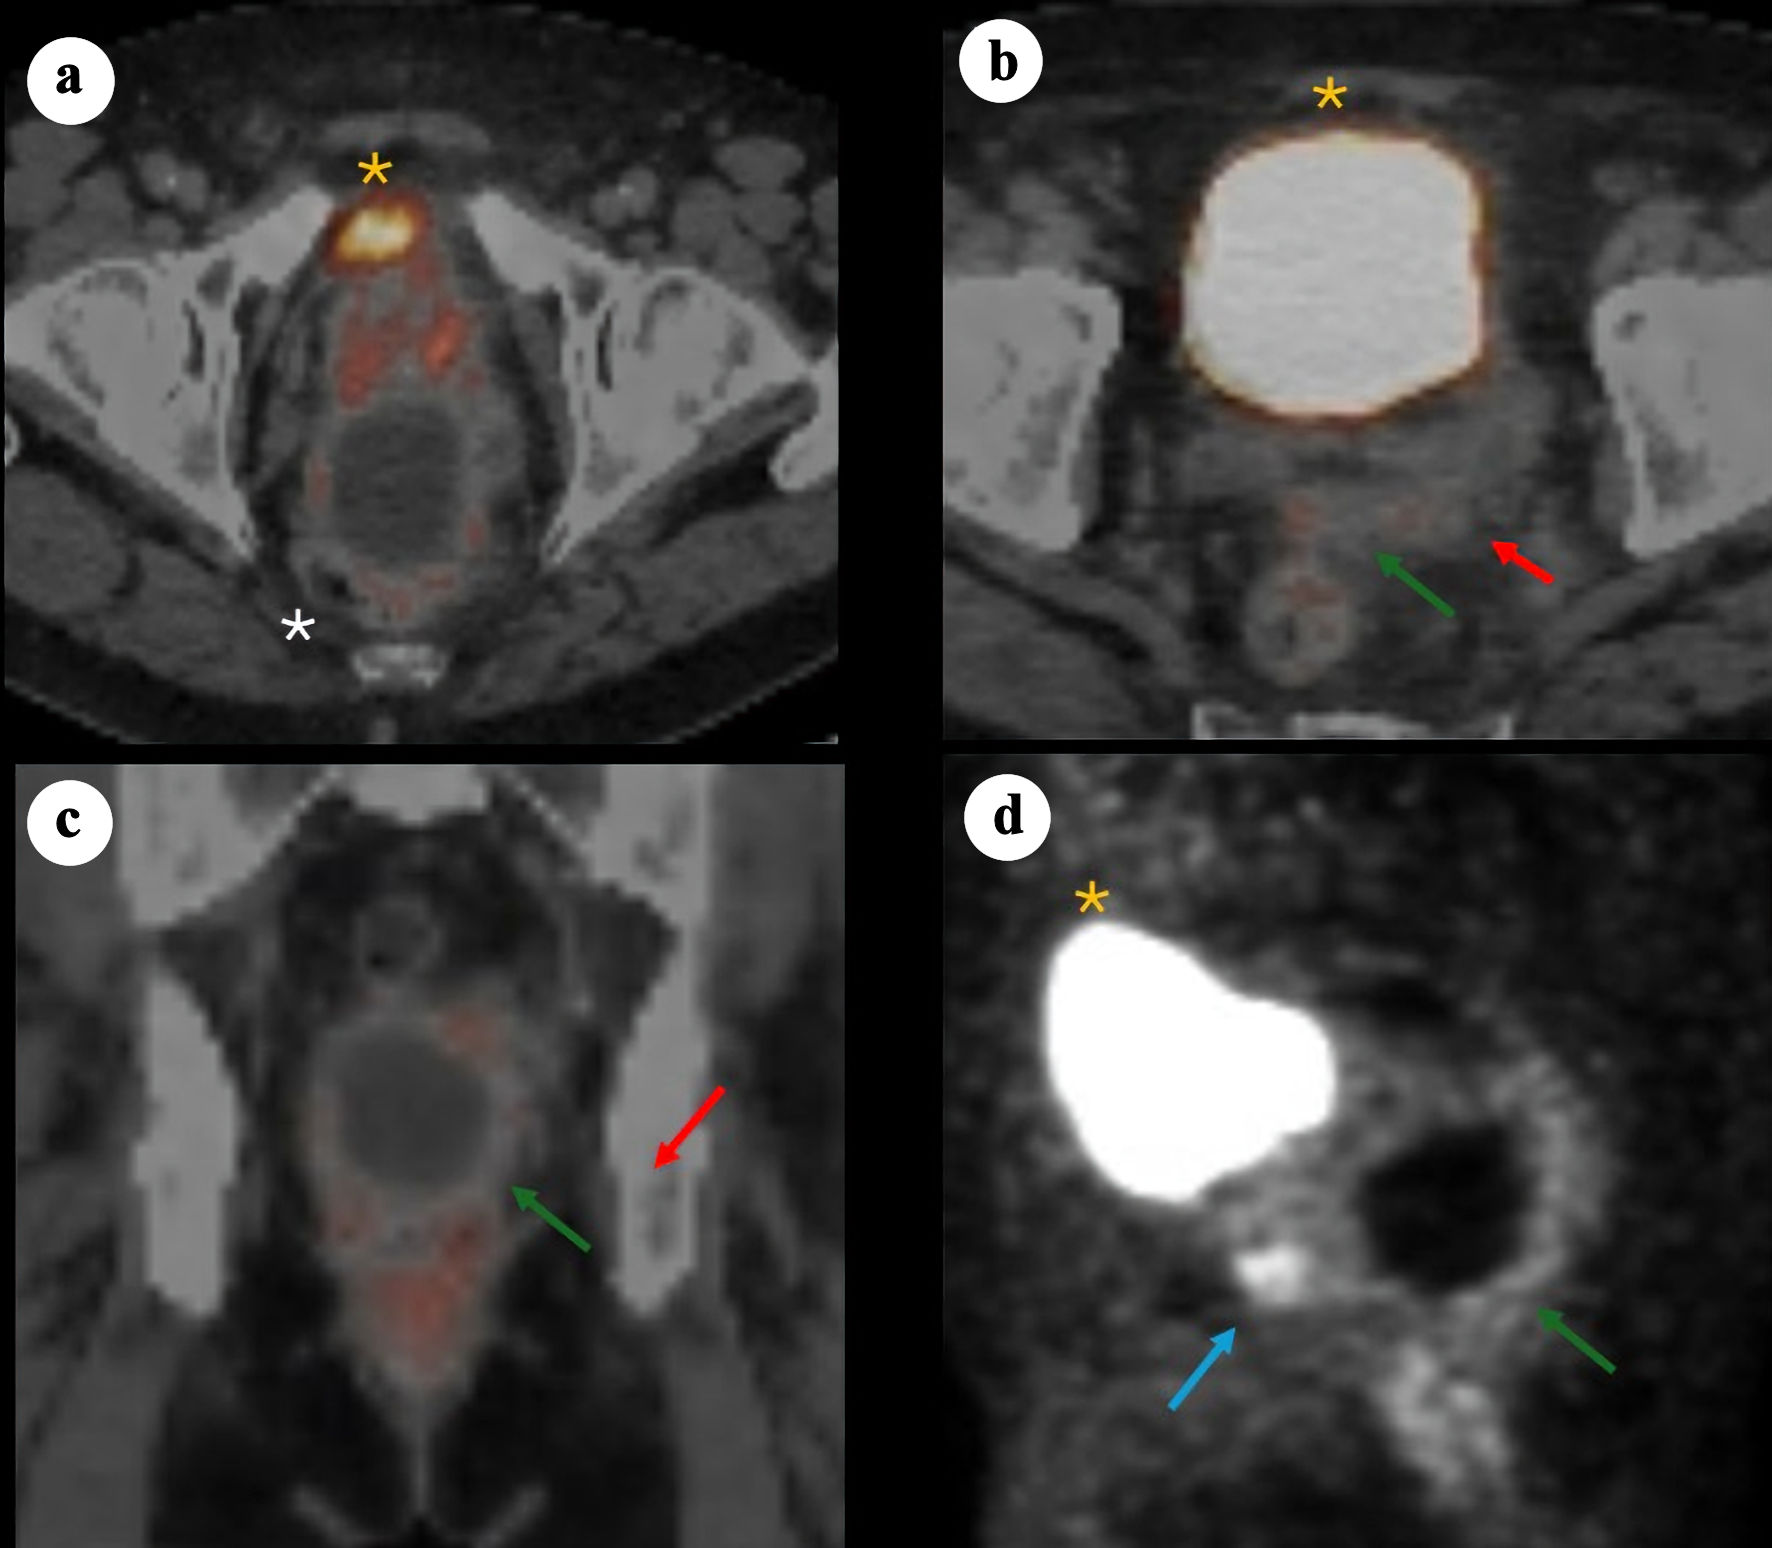

In June 2024, prostate-specific membrane antigen (PSMA) positron emission tomography/computed tomography (PET/CT) (Fig. 2) demonstrated PSMA-avid foci in the anterior midline apex, left lateral margin of the prostate, and base of the right SV. The perirectal cystic lesion showed only low-level PSMA uptake in its wall. There was no evidence of nodal or osseous metastases. Mild left hydronephrosis and hydroureter were noted, with the point of obstruction near the left SV.

Figure 2. 68Ga-PSMA PET/CT images demonstrating a large cystic mass in the pelvis consistent with primary SV adenocarcinoma. (a) Axial PET/CT showing bladder anteriorly (yellow asterisk), prostate (minimal PSMA uptake) and adjacent cystic pelvic mass (white asterisk). (b) Axial PET/CT showing bladder anteriorly (yellow asterisk), with posterior a solid component (red arrow) arousing from the left SV and contiguous tissue extension (green arrow). (c) Coronal fused PET/CT showing the relationship between the cystic mass and the adjacent prostate/SV region, with the solid enhancing component (red arrow) and soft tissue extension (green arrow). (d) Sagittal PET maximum intensity projection illustrating the prostate solid lesion component (blue arrow) and cyst (green arrow) posterior and caudal to the bladder (yellow asterisk). PSMA: prostate-specific membrane antigen; PET/CT: positron emission tomography/computed tomography; SV: seminal vesicle.